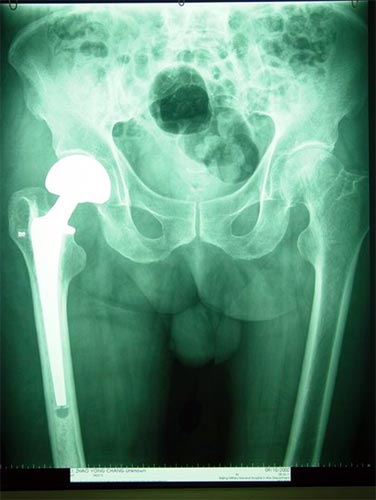

病例五

患者男性,76岁,十年前曾右髋关节置换术,术后逐渐出现髋关节疼痛活动受限,

X线片显示股骨假体和髋臼均松动,股骨近段有骨缺损。

行翻修手术。术中发现臼底已经穿透入盆腔,用钛网和植骨方法修复髋臼,股骨侧用非骨水泥假体固定。